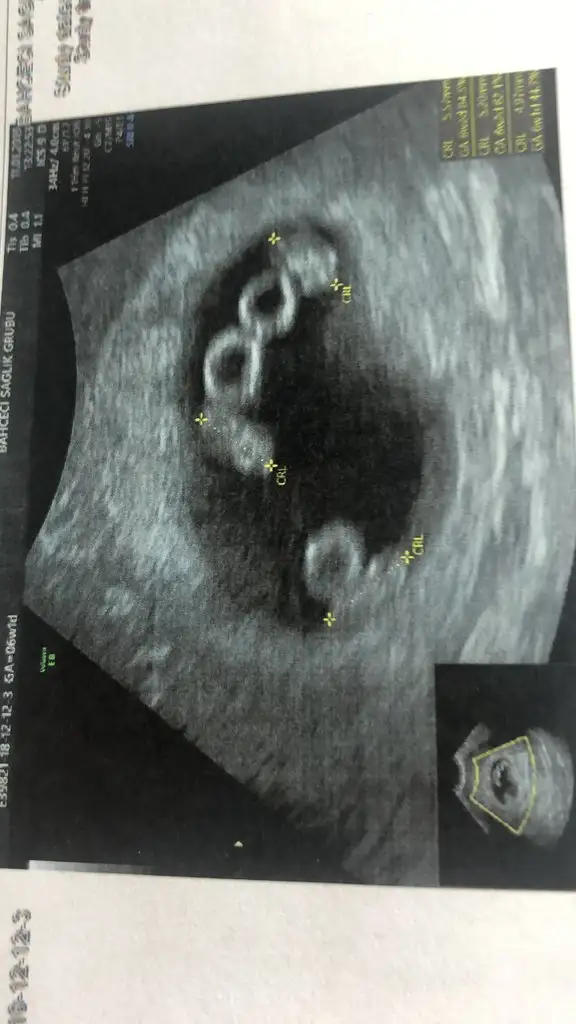

Evet imiz nasip etti rabbim cok sukur 8 ci haftaya girdik ins öyle sağlıkla devam eder korkuyorum bazen cok😔

Yok canm ilki 3 ay onceydi tek emrio koydular ücuz oldu kalpleri durdu 10. Haftada tek kesede beslenmeleri cok zordu milyonda bir bisey simdi tekrar transfer oldum cogalma ihtimali var dediler dua edicez ilk tutsun die sonra cogalmasin die ama sen korkma bak benimkiler ayni kesedeydiler seninki ayri kese onemli

Ay canım benim ya allah dualarinizi kabul etson hayirlisiyla hayirli saglikli evlat olsun ins benim minikler simdilik böyle doktor da en sevdiğimiz ikiz gebelik tipi ayrı kese dedi ama insan yinede endişeleniyor herşeyden